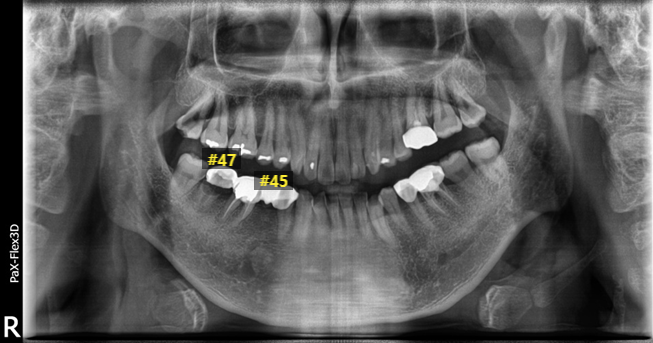

(전, 후) 2022년 2월 17일

이 환자분은 아직도 기억이 많이 남는데요.

저희 디데이치과는 서울 강남구 역삼동 선릉역 근처에 위치해있는데, 약 2시간 정도 걸리는 충청북도에서 내원해주신 환자분입니다.

저희 블로그 글들을 보시고 오래걸리고 멀더라도 믿을 수 있는 곳이라는 확신이 생겨 꼭 진료받고 싶다고 내원해주신 환자분이라 너무 감사하고 뿌듯해서 잊혀지지 않더라구요 ^^

환자분은 오른쪽 아래 어금니 #47과 #45는 이미 상실된 상태였구요, #46 신경치료 후 크라운하면서 #44~47 4개 치아를 브릿지로 연결해둔 상태였습니다.

엑스레이를 촬영해보니 #47의 치아 뿌리가 남아있는 상태라 이를 완전히 발치하고, 이미 상실한 #45도 바로 임플란트 식립하게 되었습니다.

다행히 잇몸뼈는 충분히 남아있고 또 튼튼한 상태라 당일 식립에 문제가 없었고 바로 임플란트 2개를 식립할 수 있었습니다.

환자분 역시 2개의 임플란트를 식립했음에도 불구하고 최종 보철물 완료까지 약 3개월 정도 소요되셔서 치료 기간을 단축할 수 있었습니다.